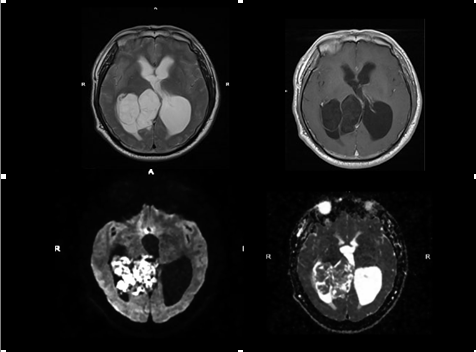

3、胆脂瘤与蛛网膜囊肿鉴别:胆脂瘤含大量肌固醇晶体和脂肪会限制水分了的弥散运动,从而DWI为高信号,ADC为低信号;蛛网膜囊肿含脑脊液样液体,弥散不受限,从而DWI为低信号,ADC为高信号;